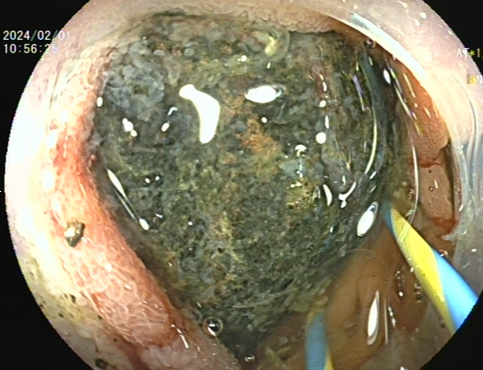

一位70多岁的阿婆,因多次空腹吃柿子后导致腹痛、呕吐来到我院就诊,经胃镜检查发现患者的胃和小肠上段存在巨大胃石嵌顿。

巨大胃石)                (小肠上段巨大胃石嵌顿)

我院消化内科团队接诊后,立即为患者安排胃镜并清除胃石。然而,还有一颗巨大胃石嵌顿在小肠,由于小肠深、远,操作困难,利用圈套器及斑马导丝等方法均无法碎取嵌顿的胃石。与此同时,嵌顿的胃石已把小肠卡得缺血变紫,如不尽快把胃石取出来,阿婆只能“开腹取石”。然而,阿婆1个月前才因为“肠梗阻”进行了一次开腹手术,她非常希望医生能不用开刀就把小肠里的结石取出来。

术中,潘新智主任娴熟地操控内镜通过胃、十二指肠降段,水平段,抵达空肠上段找到嵌顿胃石,在泌尿外科彭溪主治医师协助下,直视下利用钬激光精准地把巨大胃石碎成5块,排向远方。术后患者腹痛缓解,大便通畅,顺利出院。